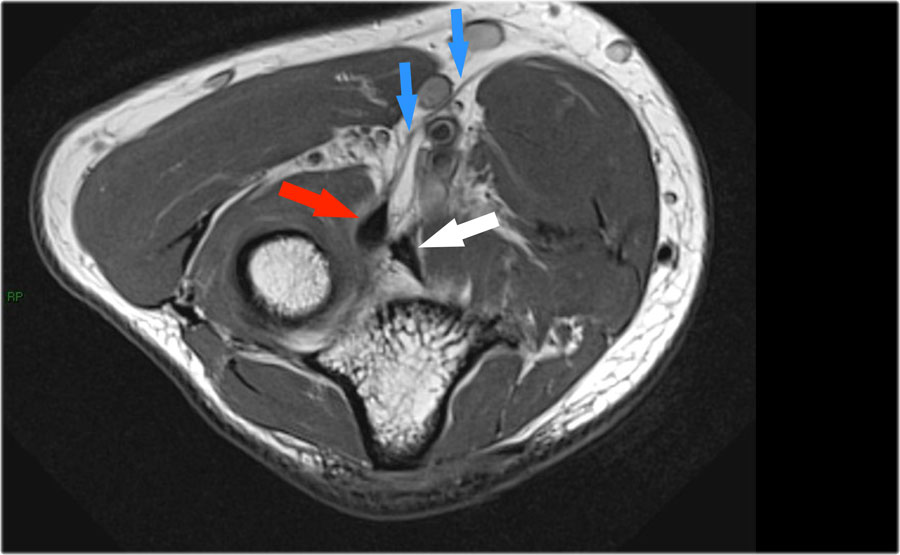

Cuộn qua các hình ảnh cắt ngang của gân cơ nhị đầu từ chỗ nối cơ-gân đến điểm bám tận trên lồi củ xương quay.

Bệnh lý của gân cơ nhị đầu đoạn xa rất giống với bệnh lý của gân Achilles.

Có thể gặp thoái hóa gân, rách một phần và rách hoàn toàn có hoặc không có sự co rút.